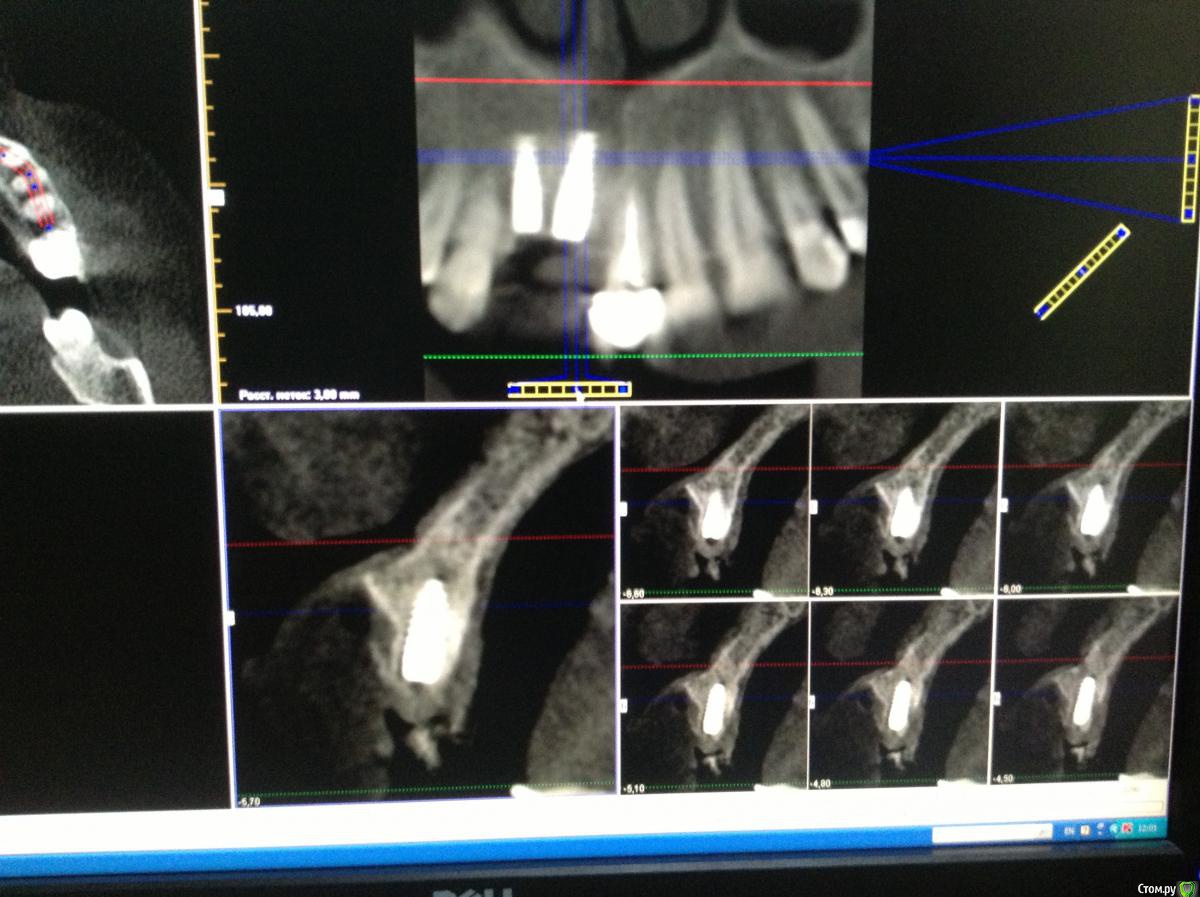

Pro100Andre Опубликовано 5 июня, 2015 Поделиться Опубликовано 5 июня, 2015 У пациента более 7 лет отсутствует зуб 11, мостовидный протез 12-21 функционировал все это время, но нынешнее состояние требует его замены. Зуб 12 на удаление, подскажите как быть удалить 12 и сразу поставить два имплантата, присыпать ауто с максграфтом под мембрану или растянуть на несколько этапов? Ссылка на комментарий

Pro100Andre Опубликовано 5 июня, 2015 Автор Поделиться Опубликовано 5 июня, 2015 12 терапевты усмотрели резорбцию корня говорят не стоит оставлять, если в два этапа не ухудшит ли это прогноз для 11? да еще 12 под медиальным наклоном стоит, если имплантат ставить то ближе к клыку получится думаю стабилизация первичная норм будет Ссылка на комментарий

Pro100Andre Опубликовано 10 июля, 2015 Автор Поделиться Опубликовано 10 июля, 2015 Вот так получилось 12 терапевты не решились перелечивать Ссылка на комментарий